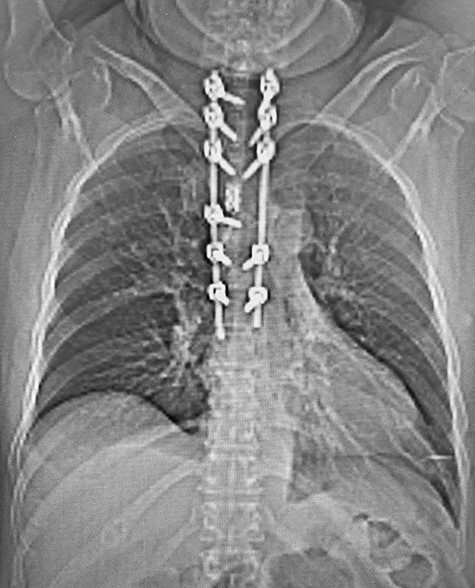

Spinal images are presented in Figs 1–6. Cross-sectional imaging revealed no other neoplastic lesion. He received dexamethasone 10 mg bolus then 4mg four times daily with appropriate proton pump inhibitor coverage. Due to no distinguishable major arterial feeder upon review of the imaging jointly with the neuroradiologist, pre-operative embolization was not attempted. The following morning, he underwent posterolateral right costotransversectomy, ligation of the ipsilateral T4 nerve root, T4 vertebrectomy and insertion of an expandable titanium cage with T1–T7 pedicle screw fixation (Figs 7 and 8). Post-operatively his pain improved to VAS 2/10 and motor power in his left lower limb improved to MRC grade 4/5. The patient was discharged home Day 10 post-admission with physiotherapy.

Post-operative CT with reconstructed anteroposterior view of the T1–T7 pedicle screw fixation and expandable titanium cage in situ.